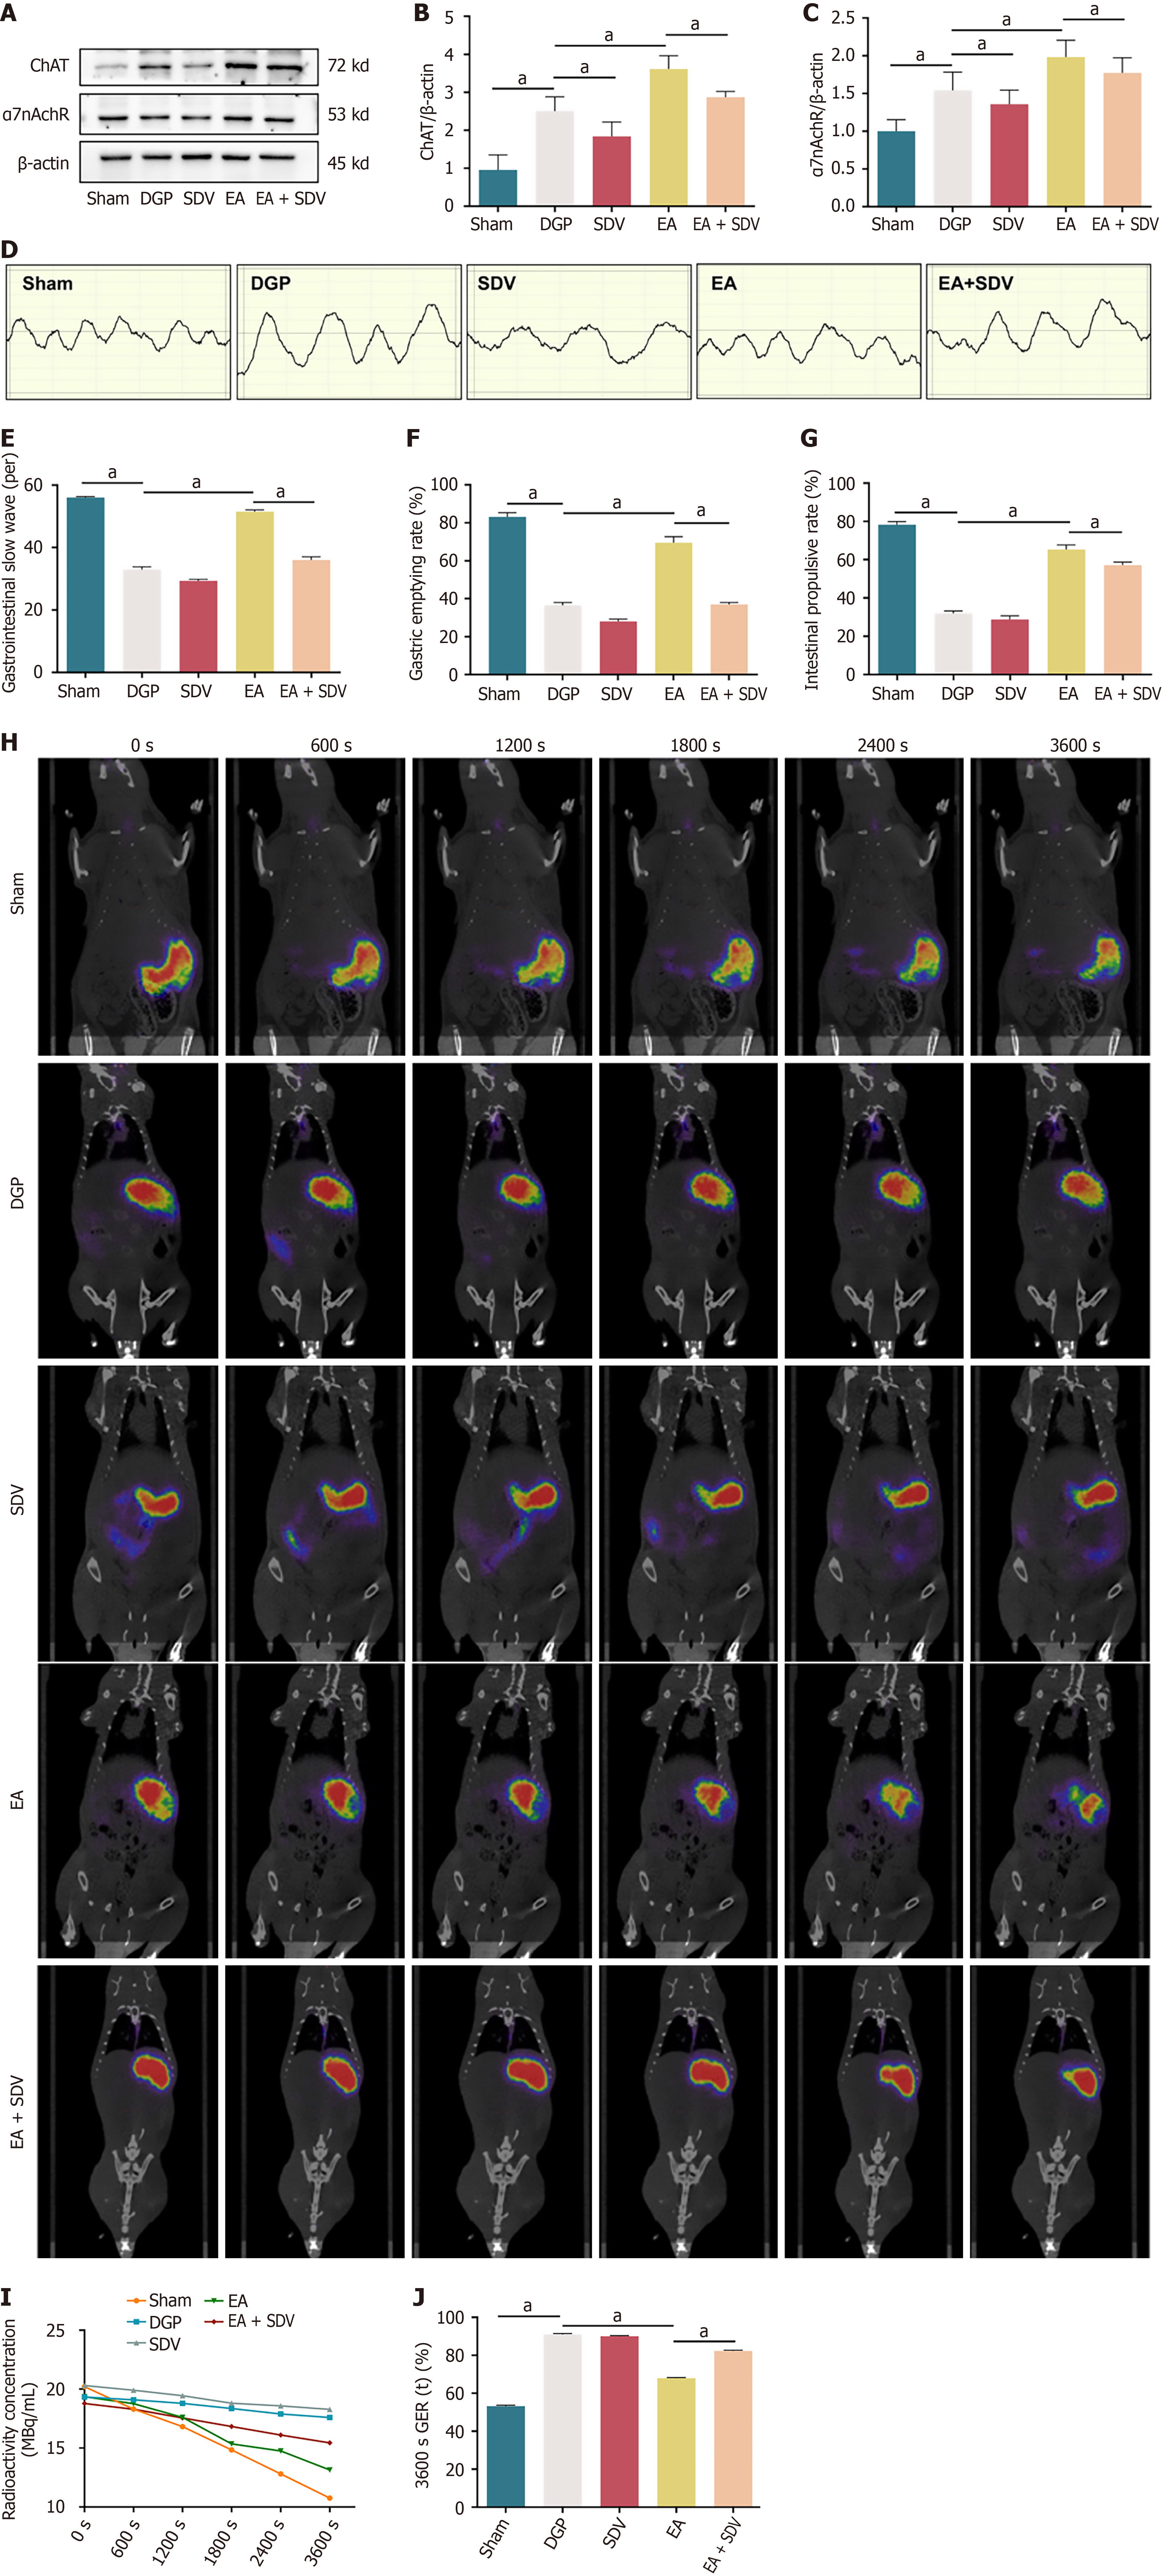

Utilizing the preceding evidence that EA activates the NTS through vagal afferent pathways, the present study investigated the role of vagal efferent signalling in EA-mediated gastric motility restoration by performing SDV in DGP rats. The results of the western blot analysis revealed a significant reduction in the expression of ChAT and α7nAChR in the stomach of the rats in the SDV group compared to the DGP group (P < 0.05). In contrast, EA significantly increased the expression of both proteins (P < 0.05). Crucially, SDV abolished EA-induced ChAT/α7nAChR activation (P < 0.05), confirming that EA’s therapeutic effects require intact vagal efferent signaling (Figure 7A-C). Electrogastrography demonstrated that EA restored gastric slow wave discharges in DGP rats (P < 0.05), an effect that was attenuated by SDV (P < 0.05; Figure 7D and E). The findings were corroborated by functional assessments: EA improved both gastric emptying and small intestinal propulsion rates (P < 0.05), whereas SDV negated these improvements (P < 0.05; Figure 7F and G). Dynamic PET-CT imaging further validated the prokinetic effects of EA, showing accelerated gastric radioactivity clearance in rats treated with EA (67.8% retention at 3600 seconds) compared to rats treated with DGP (90.9% retention; P < 0.05; Figure 7H and I). Post-spontaneous duodenal vagus stimulation (SDV), the efficacy of EA was significantly diminished, with residual gastric content increasing to 82.2% (P < 0.05; Figure 7J). The collective findings of this study demonstrate that EA enhances gastric motility via the subdiaphragmatic vagus nerve, thereby establishing it as a critical efferent pathway for neuromodulation in DGP.